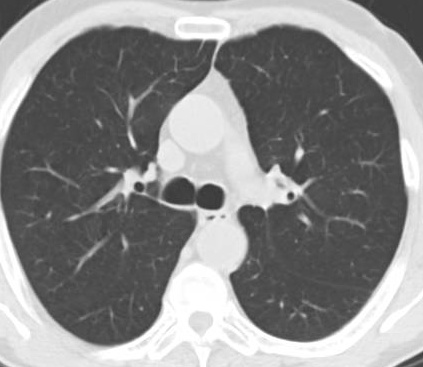

İnönü Üniversitesi Tıp Fakültesi Biyoistatistik ve Tıp Bilişimi Anabilim Dalı tarafından tasarlanan açık kaynak erişimli yapay zekâ tabanlı yazılım prototiplemesi ile covid-19 tanısında hekimlere klinik destek sağlayabilecek bir modelin geliştirilmesi hedeflenmektedir.

Toraks (göğüs) Bilgisayarlı Tomografi (BT)

cihazlarından alınan görüntüler kullanılarak derin öğrenme ve görüntü işleme tabanlı bir model oluşturulmuştur. Tasarlanan bu eğitilmiş model sayesinde covid-19 sınıflandırılması geliştirilen web tabanlı yazılım prototiplemesi ile yapılabilmektedir.